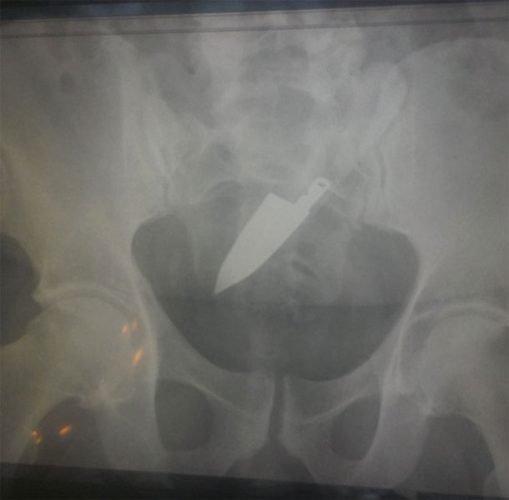

9-Uma faca

Como essa pessoa conseguiu inserir uma faca dentro de seu corpo através do seu ânus nós não sabemos. Mas, inicialmente, ela parece ter sido colocada primeiramente pelo cabo. Isso deve ter sido realmente doloroso e gerado enormes consequências. Infelizmente não sabemos o destino que se deu para essa pessoa.